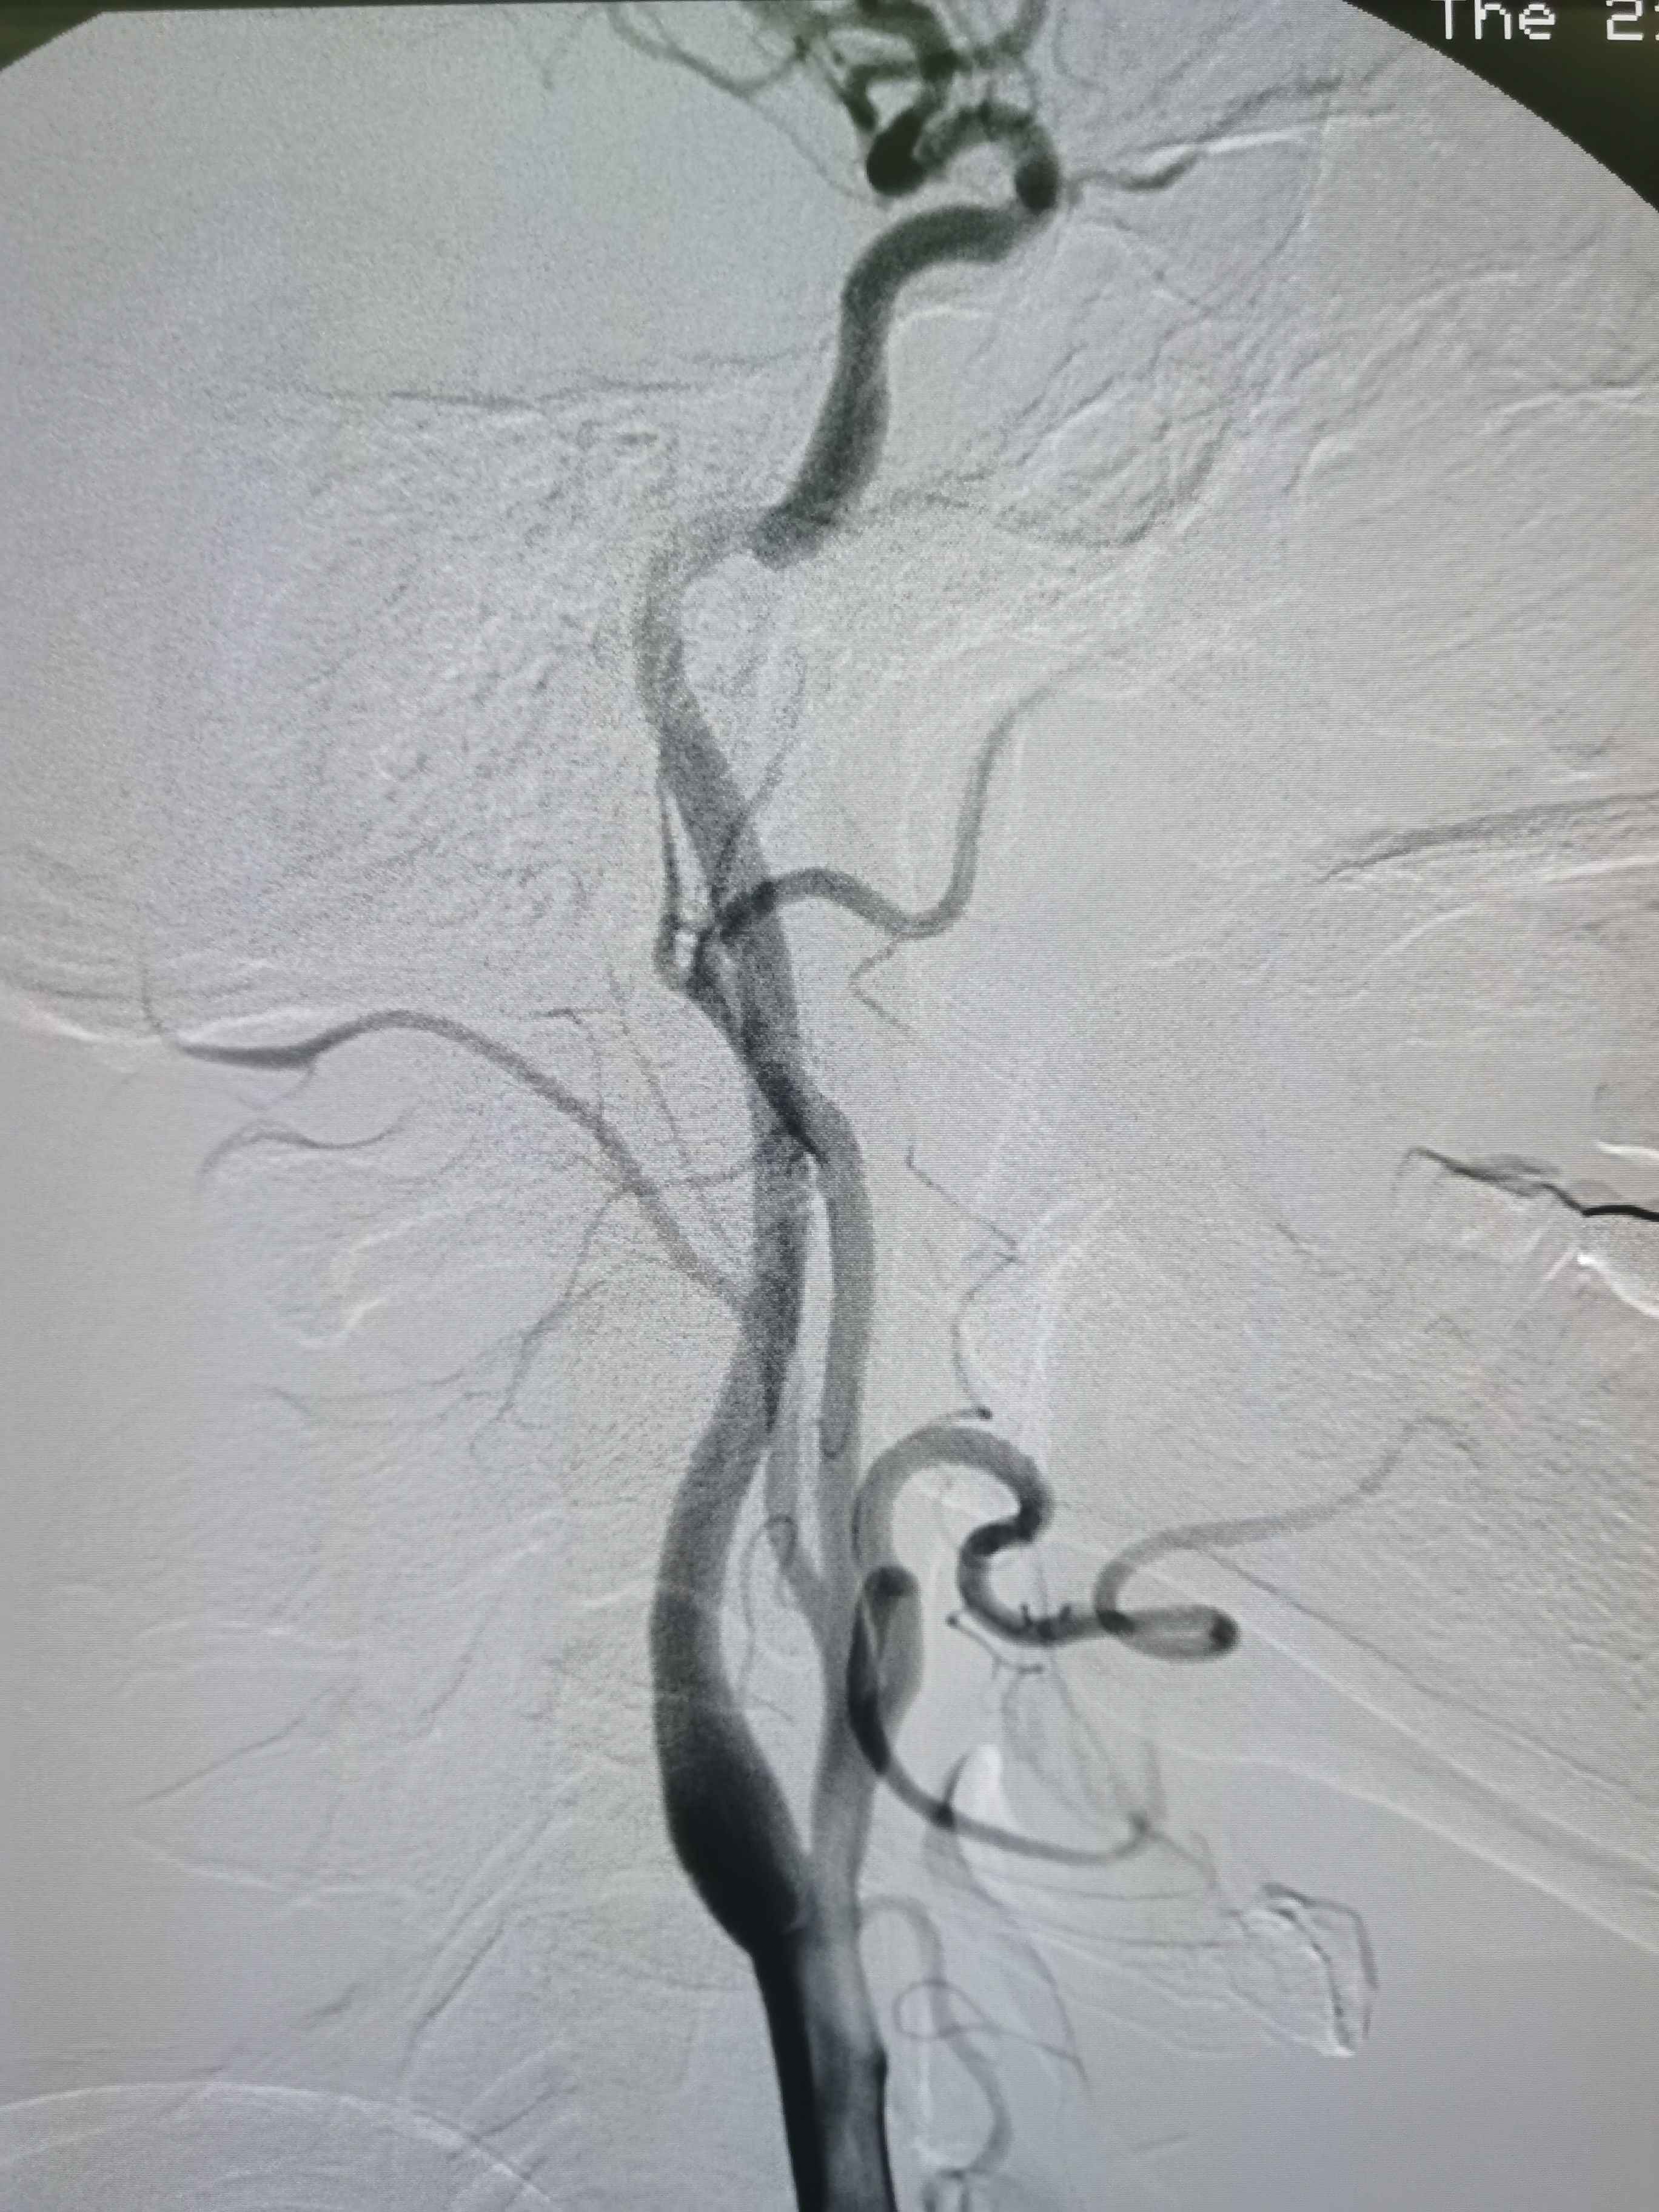

术前术后对比

1、本例患者系因左侧大脑中动脉急性闭塞出现左侧半球梗死,系责任血管。

2、造影评估见左侧大脑中动脉起始段闭塞,但动脉晚期可见远端血管返流显影,考虑闭塞段较短,且为新近闭塞,具备介入治疗指征。

3、球囊扩张后血管狭窄解除,无夹层及弹性回缩,遂未再植入支架,术后继续药物治疗,定期随访。